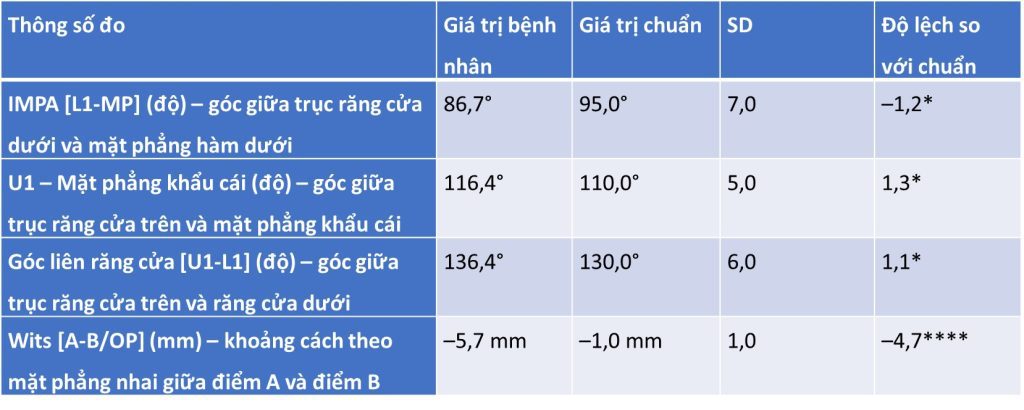

- Khớp cắn bù trừ với răng cửa hàm trên nghiêng ra trước và răng cửa hàm dưới nghiêng vào trong

- Chỉ số Wits loại III

- IMPA thấp hơn chuẩn 1,2 SD → răng cửa dưới hơi nghiêng vào trong.

- U1–Palatal plane cao hơn chuẩn 1,3 SD → răng cửa trên nghiêng ra trước.

- Góc liên răng cửa cao hơn chuẩn 1,1 SD → khớp cắn bù trừ (răng cửa trên nghiêng ra, răng cửa dưới nghiêng vào).

- Wits âm nhiều (–5,7 mm, lệch 4,7 SD) → đặc trưng của sai khớp cắn hạng III xương.